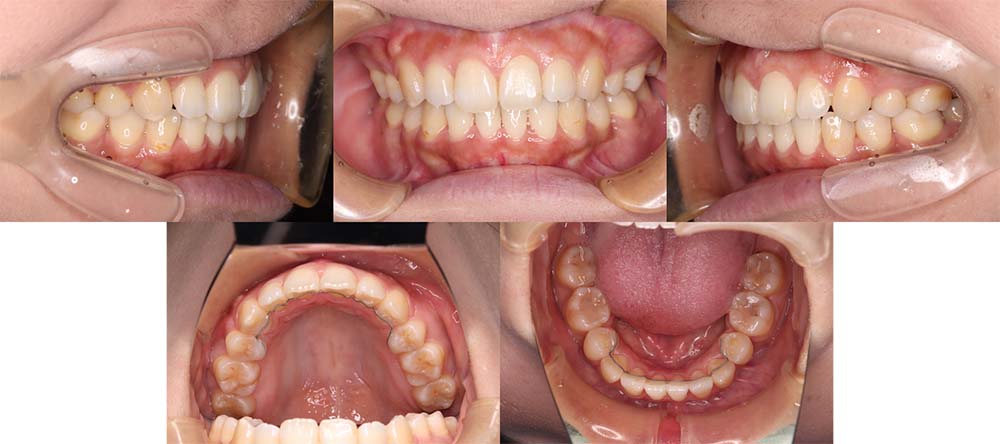

| 症例分類 | 叢生 |

| 診断名 | 上下叢生 |

| 主訴 | 八重歯と下の歯のガタガタが気になる |

| 年齢 | 24歳4ヶ月 |

| 性別 | 女性 |

| 抜歯部位 | 上下左右の第一小臼歯(4本) |

| 使用装置 | 上は裏側、下は表側のワイヤー装置 |

| 治療期間 | 2年8ヶ月 |

| 保定装置 | 固定式保定装置、取り外し式保定装置(8時間) |

| 費用 |

[検査・診断料] ¥49,500 [基本施術料] ¥1,056,000 [調整料] ¥5,500/回 [抜歯] ¥5,500/本 [保定装置] ¥55,000(税込) 抜歯や虫歯治療は他院にて費用が別途かかります。(抜歯¥4,000〜10,000/本)

上下叢生のため、上下第一小臼歯を抜去して上裏側下表側のハーフリンガルで治療しました。

顎間ゴムは治療期間の半年程度使用しましたが、協力度が良好だったためしっかり咬合することができました。

治療開始前にホワイトニングをしたこと、咬合力が強いためか装置の脱離が多く、予定より治療期間が伸びてはしまいました。